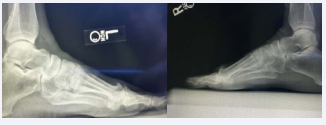

Before any treatments are offered a series of radiographs should be taken to assess the pathology of the first MPJ. This usually consists of the lateral, anteroposterior, and the medial oblique views of the affected foot. The AP view allows the practitioner to assess the joint space, while the lateral and MO views will show any associated spurring around the joint as well as the joint space. Occasionally loose bodies or sub chondral cysts are seen in any view taken. Sclerosis of the bone may also be seen on the radiographic studies since this is one of the ways that the bone tries to heal itself (Figure 1-4).

Figure 3: This is the radiograph of a patient whose initial surgery consisted of a hemi implant. The patient was not doing well with this type of implant and decided to undergo a second procedure and have it converted using the Arthrosurface total implant

Figure 4: In this radiograph, there are substantial cystic changes occurring in the first metatarsal head. There is also a significant loss of the joint space